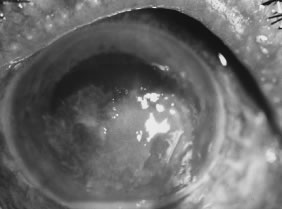

In the early stages of infection, filamentous fungi produce signs that are readily distinguishable from yeast or bacterial keratitis. The most distinctive sign is the presence of delicate, fine, feathery, opalescent, gray-white or yellow-white material in the anterior stroma, surrounded by scant cellular infiltrate or edema (Fig. 1). The epithelium may be intact. The overlying epithelium may be granular and the surface elevated and irregular in contour. Linear infiltrates typically extend into the adjacent stroma. Multiple discrete opacities may develop outside the perimeter of the principal focus of inflammation, either separated by clear stroma or linked by fine linear collections of inflammatory cells and material (Figs. 2 and 3). In the absence of inflammation in the adjacent stroma, branching hyphal fragments may be visualized by biomicroscopy (Figs. 4 and 5). Confocal microscopy may also detect hyphal elements within the stroma.28,29 Peripheral infection resembles noninfectious marginal infiltrative and ulcerative keratitis (Fig. 6). Multifocal keratitis may develop after contact lens wear or injury by multiple projectiles (Fig. 7). In the early stages, iritis is present and the intraocular pressure remains normal. Inappropriate, empirical therapy of fungal keratitis with topical fluoroquinolone or aminoglycoside antibiotics may suppress or eliminate the superficial elements but allow extension of the organisms into the stroma because these agents may possess selective antifungal activity.4,30,31

There is no distinguishing clinical sign by which to recognize the genus or species of the infectious filamentous fungus. F. solani is the most virulent organism and typically produces rapidly progressive infection characterized by epithelial and stromal ulceration, dense stromal necrosis, abundant cellular infiltrate, and edema in the adjacent stroma and hypopyon (Figs. 8 and 9). Delicate feathery components are transient. Individual hyphal fragments are rarely visualized. Infection by certain species of Aspergillus and Scedosporium (Figs. 10 and 11) resembles F. solani keratitis and progresses rapidly. Infection by less virulent organisms, such as Curvularia and Alternaria species, produces small, focal (less than 3-mm diameter) areas of nonnecrotizing stromal inflammation with delicate feathery borders (see Fig. 1 and Fig. 12). Macroscopic pigmentation may develop in keratitis caused by Alternaria, Curvularia, and other dematiaceous fungi (Fig. 13).4,11,14 The central component may progress to dense, opaque, gray-white suppuration in the deep stroma without enlargement in total area and may be accompanied by mild inflammation in the adjacent stroma. Iritis is minimal to moderate. Infection caused by other, relatively less virulent organisms resembles herpes simplex or noninfectious keratitis (Fig. 14).